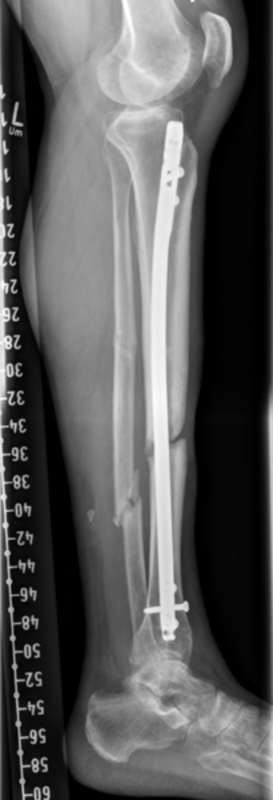

Rekonstruktion: Bei Infektverlauf mit Nachweis von Staphylococcus aureus und Staphylococcus epidermidis sowie histologischem Nachweis einer chronischen Osteomyelitis an der linken Tibia erfolgte 1,5 Jahre nach dem Unfall die Infektsanierung mit Segmentresektion und anschließend der Segmenttransport mittels Precice-Bone-Transport-Nail.

Nach etwa 2 Monaten konnte das Kompressionsdocking erfolgen. Bei weitgehender Konsolidierung über ein Jahr nach der Implantation erfolgte die Metallentfernung des einliegenden Segmenttransport-Nagels sowie die Anpassung eines Braces zur weiteren Ausbehandlung.

Resümee: Erst durch die konsequente Segementresektion konnte der Infekt eradiziert werden. Durch die Therapie mit dem noch relativ neuen Verfahren des Segmenttransportnagels konnte dem Patienten die zwar ebenfalls meist erfolgreiche, jedoch deutlich belastendere Therapie mit einem Ringfixateur erspart werden.